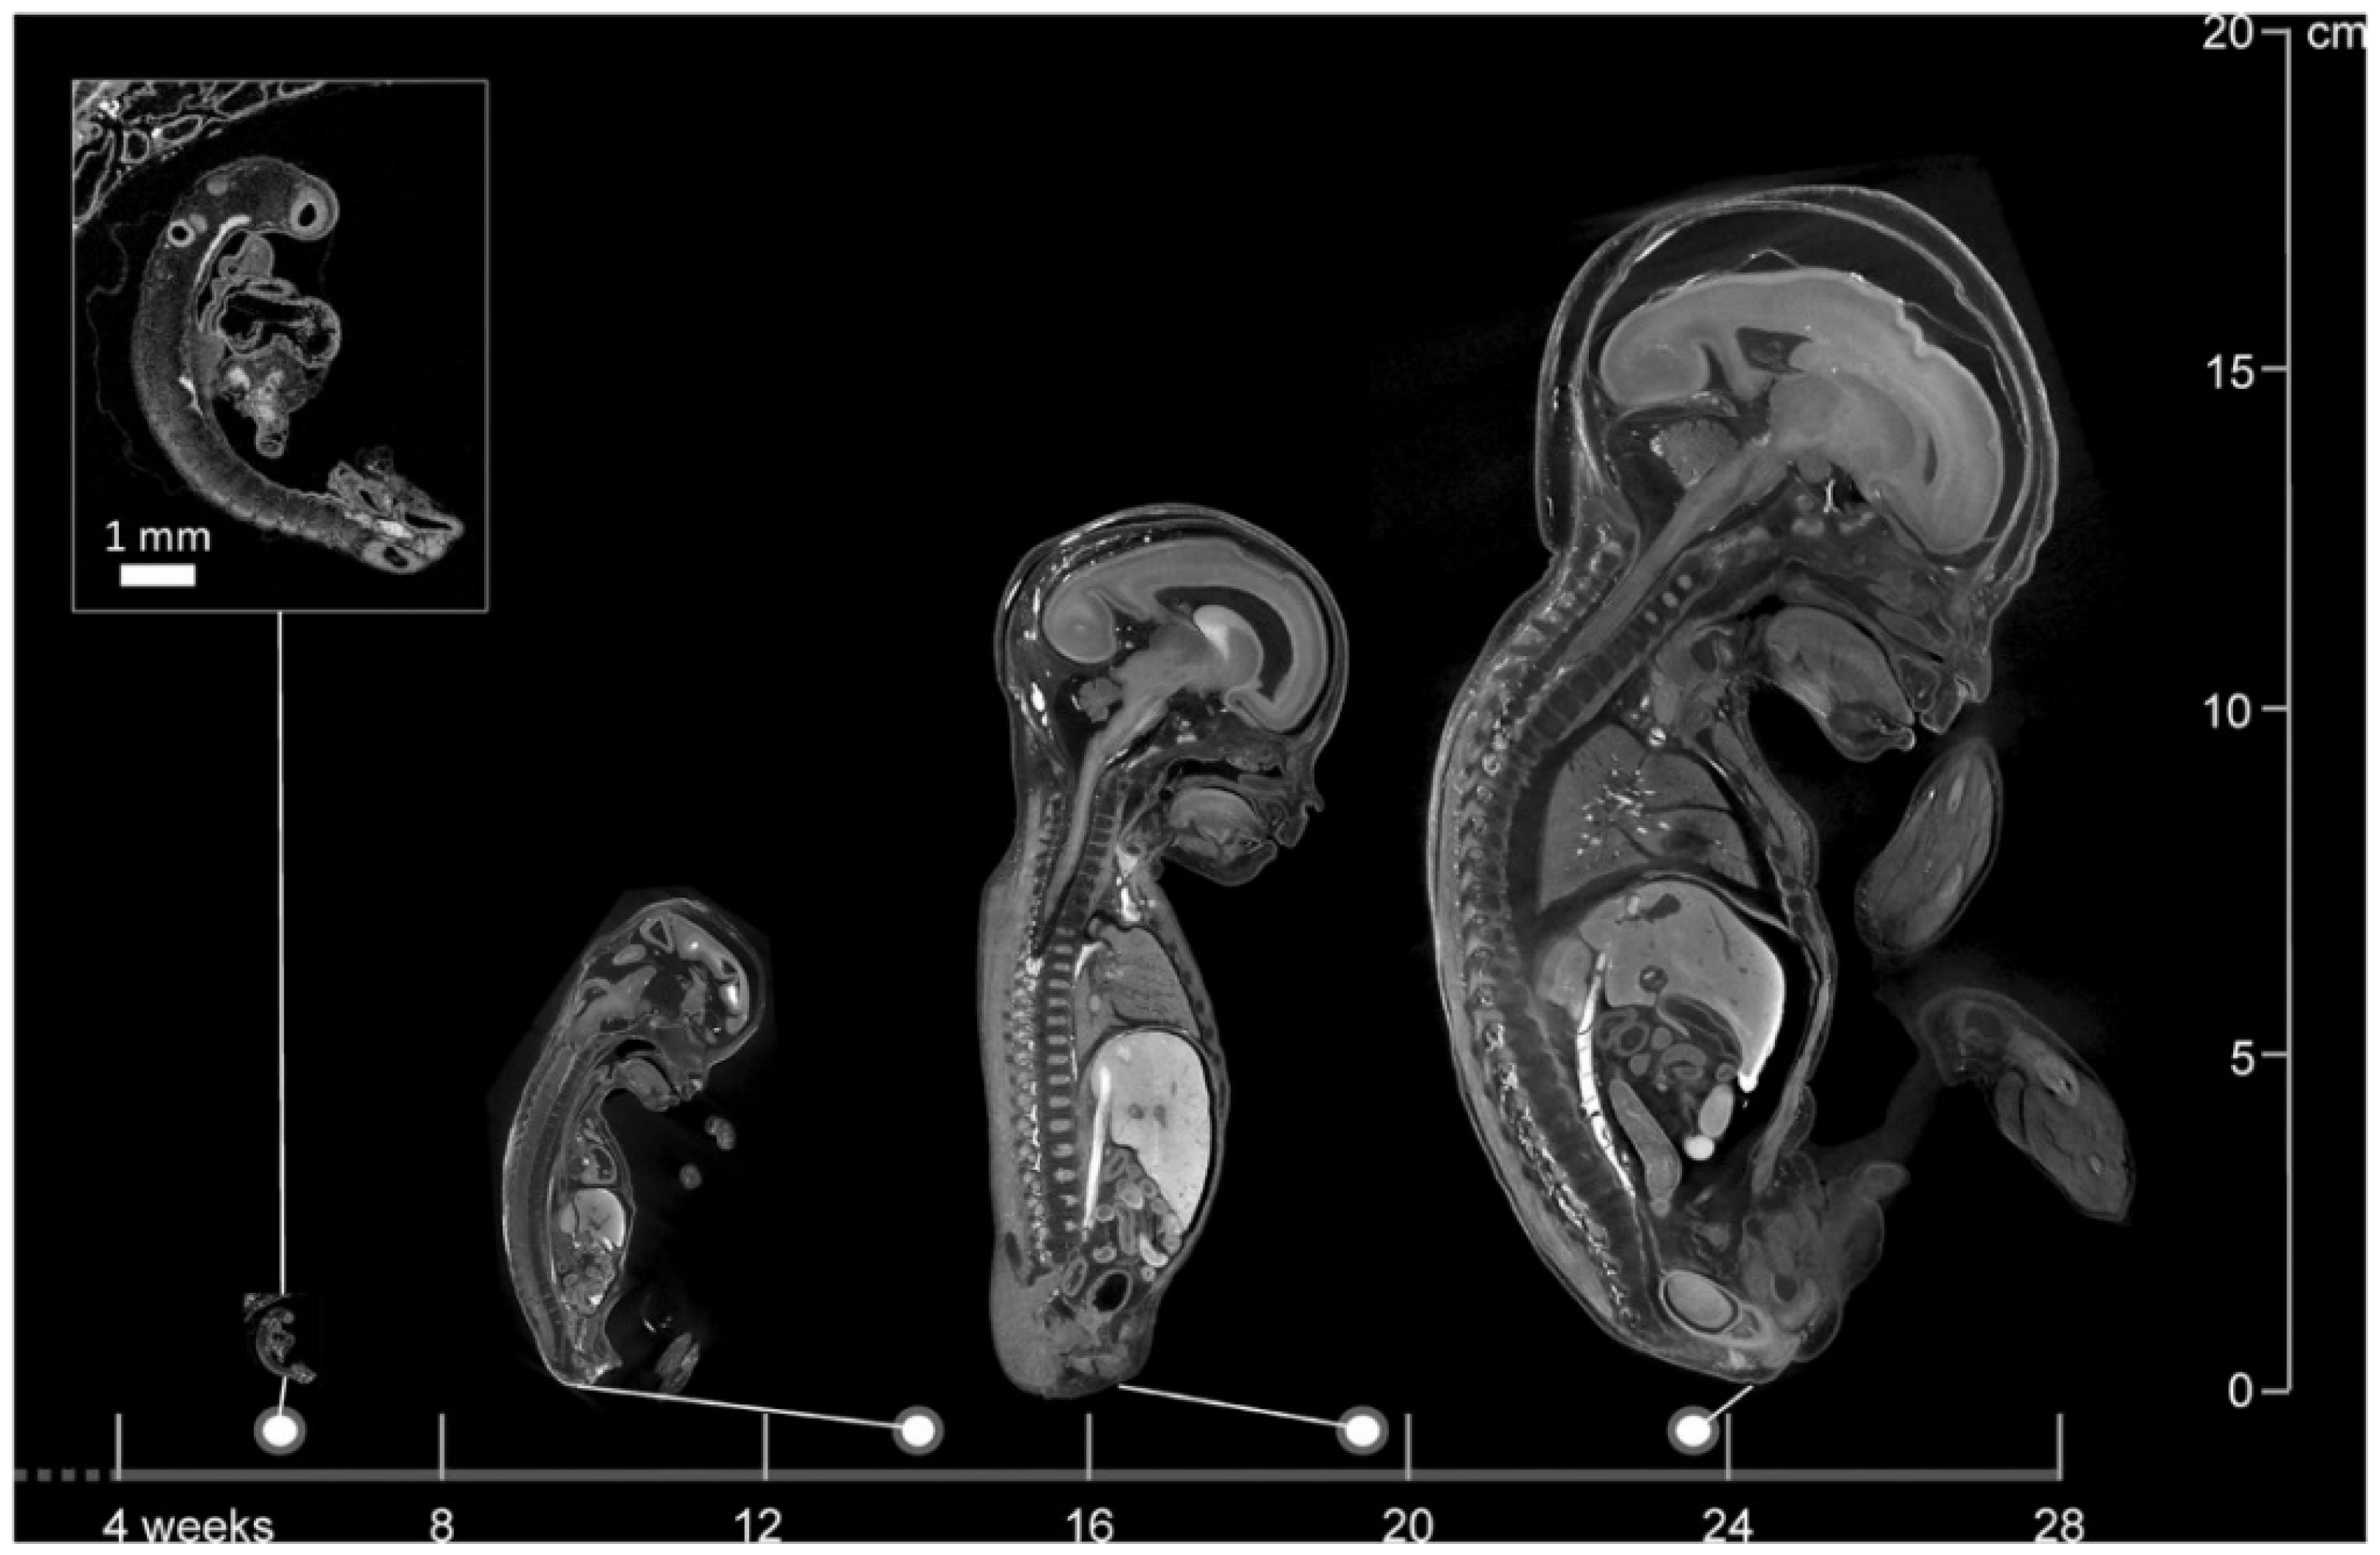

Figure 1.

Images of a 6-week-old embryo and 13-, 20-, and 24-week-old fetuses, created with micro-CT. This image illustrates the wide applicability in gestational age range of micro-CT. Scale bar represents 1 mm (Dawood et al. 2022 [62], with permission).

Using autopsy as a comparison, micro-CT appears to give promising results in identifying anatomical anomalies. A study involving 20 fetuses with gestational ages ranging from 11 to 21 weeks reported overall sensitivities of 93.8% and specificities of 100% for detecting congenital defects using micro-CT [69]. Another comprehensive study evaluating 268 micro-CT scans of fetuses between 11 and 24 weeks gestational age documented a sensitivity and specificity of 92.3% and 98%, respectively. These results imply that micro-CT serves as a good alternative to autopsy [70]. Moreover, maceration does not appear to affect micro-CT imaging quality, as high-resolution images were obtained in 95% of cases despite maceration [71]. Furthermore, micro-CT can operate on very small anatomical structures and provides increasing spatial resolution as fetal size decreases, making it a viable alternative where conventional autopsy is unfeasible (Figure 1) [62,70,72].